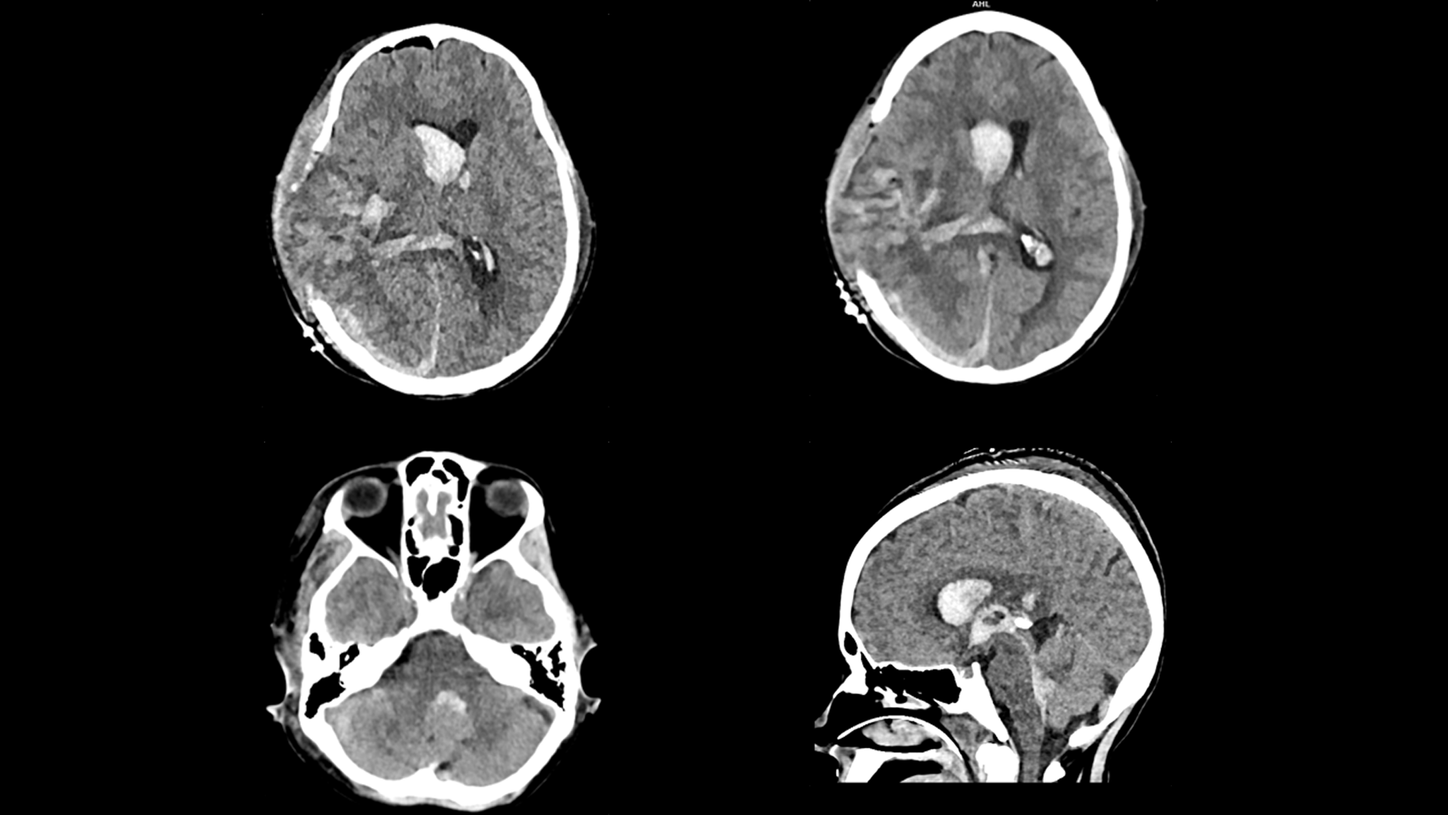

Whether portable in the Intensive Care Unit, or mobile in the ambulance as a Mobile Stroke Unit, SOMATOM On.site is designed to bring critical care imaging to your patients. With the first-of-its-kind telescopic gantry design, integrated positioning accessories, and proven SOMATOM technologies, you can achieve fast and reliable CT head imaging.

Proven SOMATOM technologies such as Stellar detector, iMAR, and ADMIRE® provide high image quality, enabling faster clinical decisions for critical care patients.

Evidence

iMAR